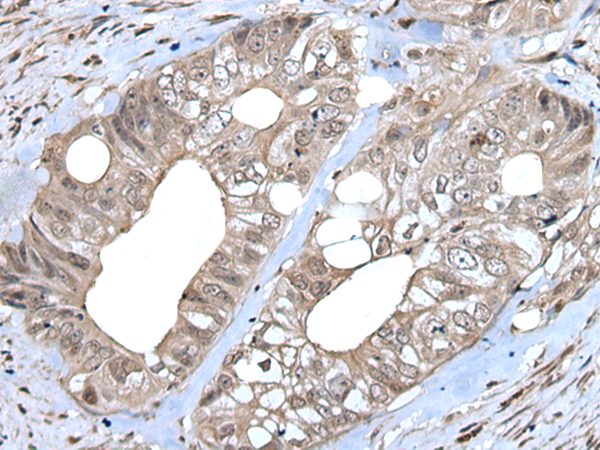

分类: 科研抗体货号: P00473别名: ICSBP; IRF-8; ICSBP1; IMD32A; IMD32B; H-ICSBP应用: IHC反应种属: Human, Mouse